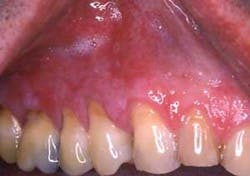

Dispersion throughout the mouth is also found in lichenoid reactions from the use of medications such as non-steoidal anti-inflammatory drugs and anti-high blood pressure medications. Figures 2 and 3 are from a patient who was taking Naprosyn. After discontinuing the medication, the tissue in Figure 3 was noticeably less inflamed. The patient took Tylenol during the two-week period and was later prescribed a different NSAID.